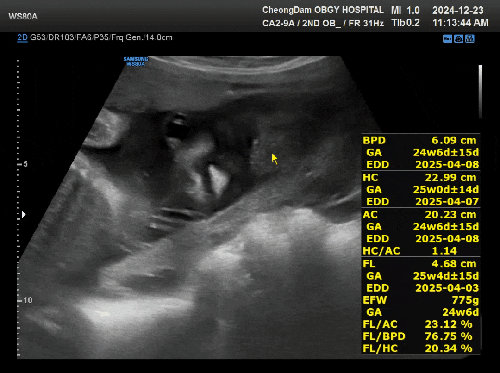

24년 12월 23일 화요일 시험관 임신 25주 2일차! * 이식일 : 24년 7월 17일 수요일 * 출산예정일 : 25년 4...